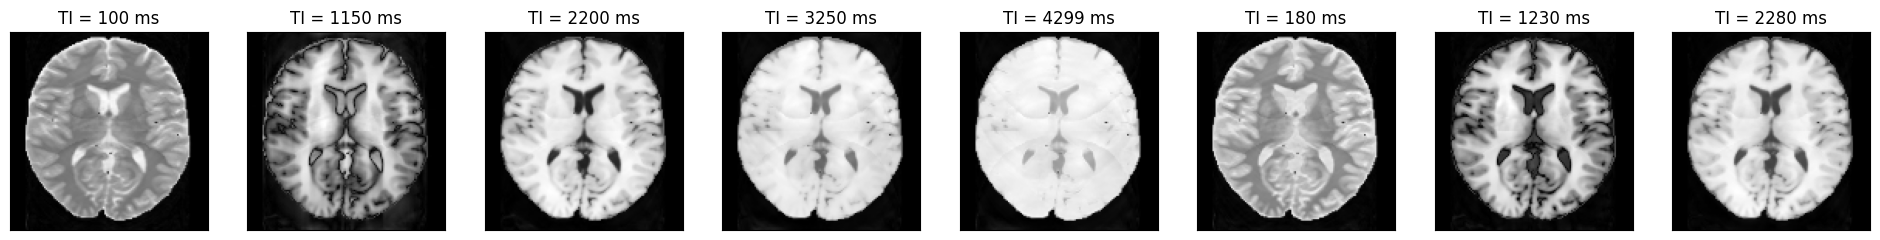

We can now plot the images at different inversion times.

idat = idata.rss().abs().numpy().squeeze()

acquisition_time_stamp = idata.header.acquisition_time_stamp.squeeze()

ti = np.concatenate(

(

idata.header.ti[0] + acquisition_time_stamp[:5] - acquisition_time_stamp[0],

idata.header.ti[1] + acquisition_time_stamp[5:] - acquisition_time_stamp[5],

)

fig, ax = plt.subplots(1, idat.shape[0], figsize=(3 * idata.shape[0], 3))

for i in range(idat.shape[0]):

ax[i].imshow(idat[i, :, :], cmap='gray')

ax[i].set_title(f'TI = {int(np.round(ti[i] * 1000))} ms')

ax[i].set_xticks([])

ax[i].set_yticks([])